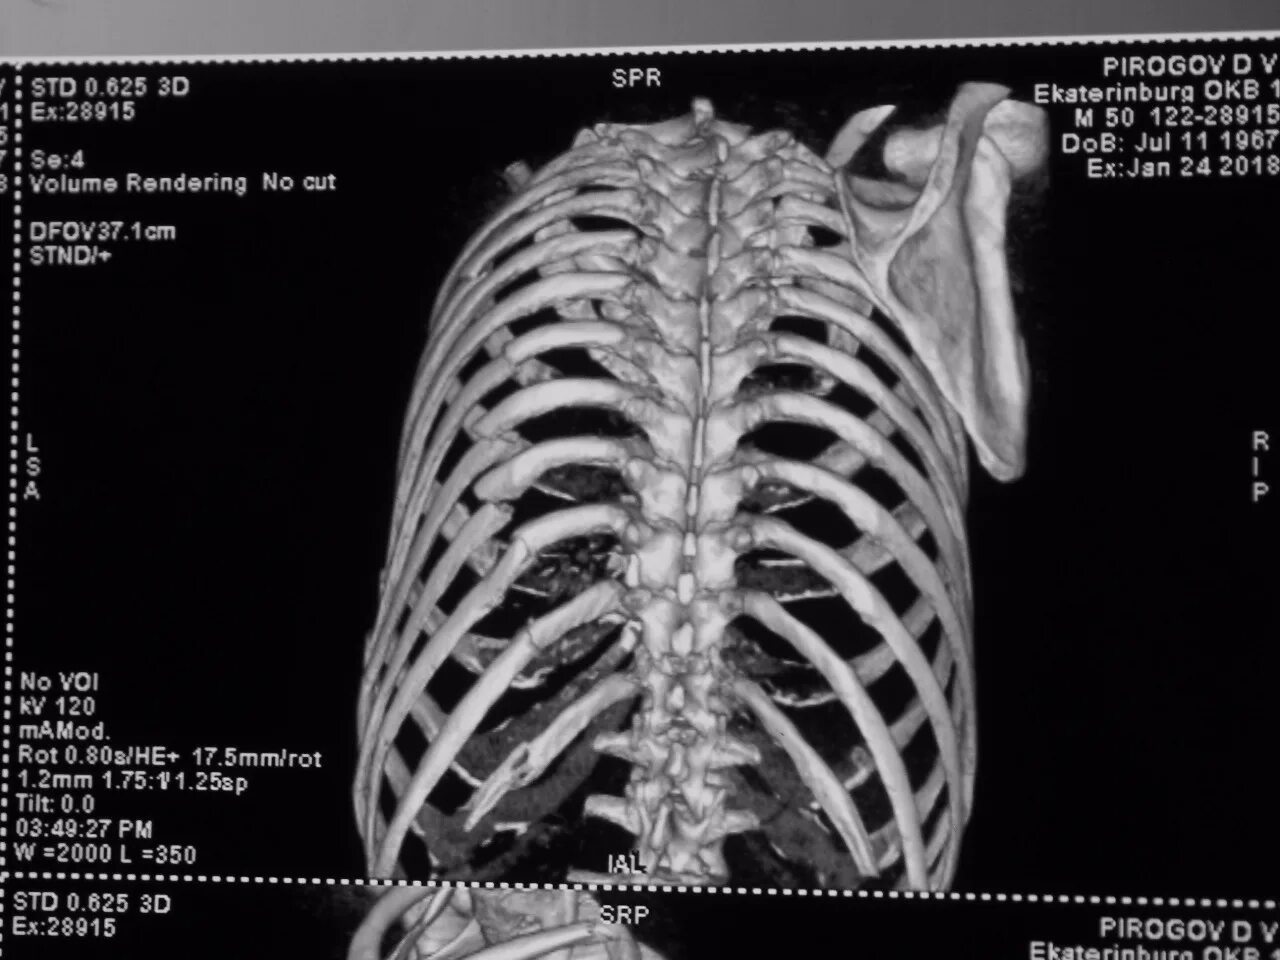

Сколько срастается ребро при переломе